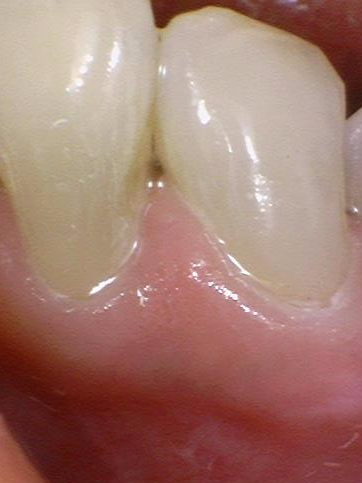

저희 치과에서 다시 레진치료를 받은 케이스입니다.

레진 떨어진 부위가 엑스레이상에도 확연히 보입니다.

타치과 3개월된 레진이 떨어져서 치아치료 전과 후